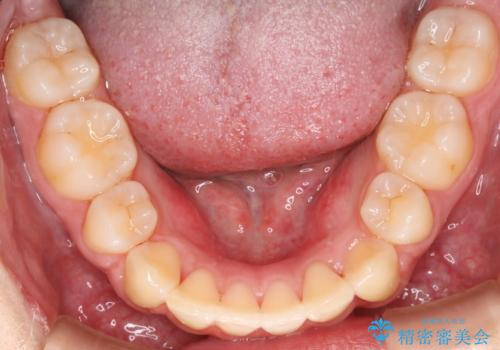

- 矯正装置

- 審美装置(ワイヤー)

- 出っ歯が気になるとご相談にいらした方です。抜歯して歯を並べました。深かった噛み合わせも改善させることが出来ました。

噛み合わせが元々深い方は一般的に噛む力が強く、治療に時間がかかる傾向にあります。治療前の想定よりも短期間でスムーズに治療を終える事ができ、大変喜んでいただけました。リテーナーによる保定もしっかり行っていただいており、後戻りなく快適にすごして頂けているとのことです。